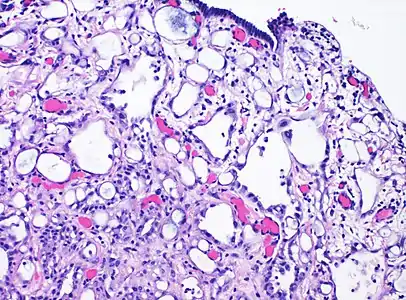

High-magnification micrograph of an adenomatoid tumor. H&E stain.

Adenomatoid tumors are rare and benign mesothelial tumors, which arise from the lining of organs. It mainly presents in the genital tract, in regions such as the testis[1] and epididymis.[2] Because of this, researchers had a difficult time concluding that type of tumor has a mesothelial origin. Immunohistochemistry staining of tumor samples show that it is indeed positive for mesothelial-markers (calretinin, WT1, and CK6).[3] It is the most common extratesticular neoplasm after lipoma, and accounts for 30% of these masses.[4] On the other hand, adenomatoid tumors are the most common tumors of testicular adnexa. Although they are more common to be found in the paratesticular region they are sometimes found in the intratesticular region. It also has been found in other organs such as the pancreas,[5] liver,[6] mesocolon,[6] and adrenal glands.[6] In the female, it has been found in the body of the uterus and the fallopian tube.[7] Most adenomatoid tumors do not cause much pain and can go unnoticed for a long time. Of course, there are a few exceptions to this absence of pain. An example of this is when adenomatoid tumors grow too close to testicular adnexal structures.[8] Tumors of this kind are usually found to be asymptomatic and easily treatable.

Given their mesothelial origin, the cells lining the spaces are positive for cytokeratins, WT1, D2-40, and calretinin. They are negative for MOC31, BerEP4, and vascular markers (CD31 or CD34). BAP1 expression is retained. L1 cell adhesion molecule (L1CAM), a marker of NF-kB pathway activation, has been shown to be expressed in adenomatoid tumors (and negative in other benign mesothelial tissues and mesothelioma).[10]